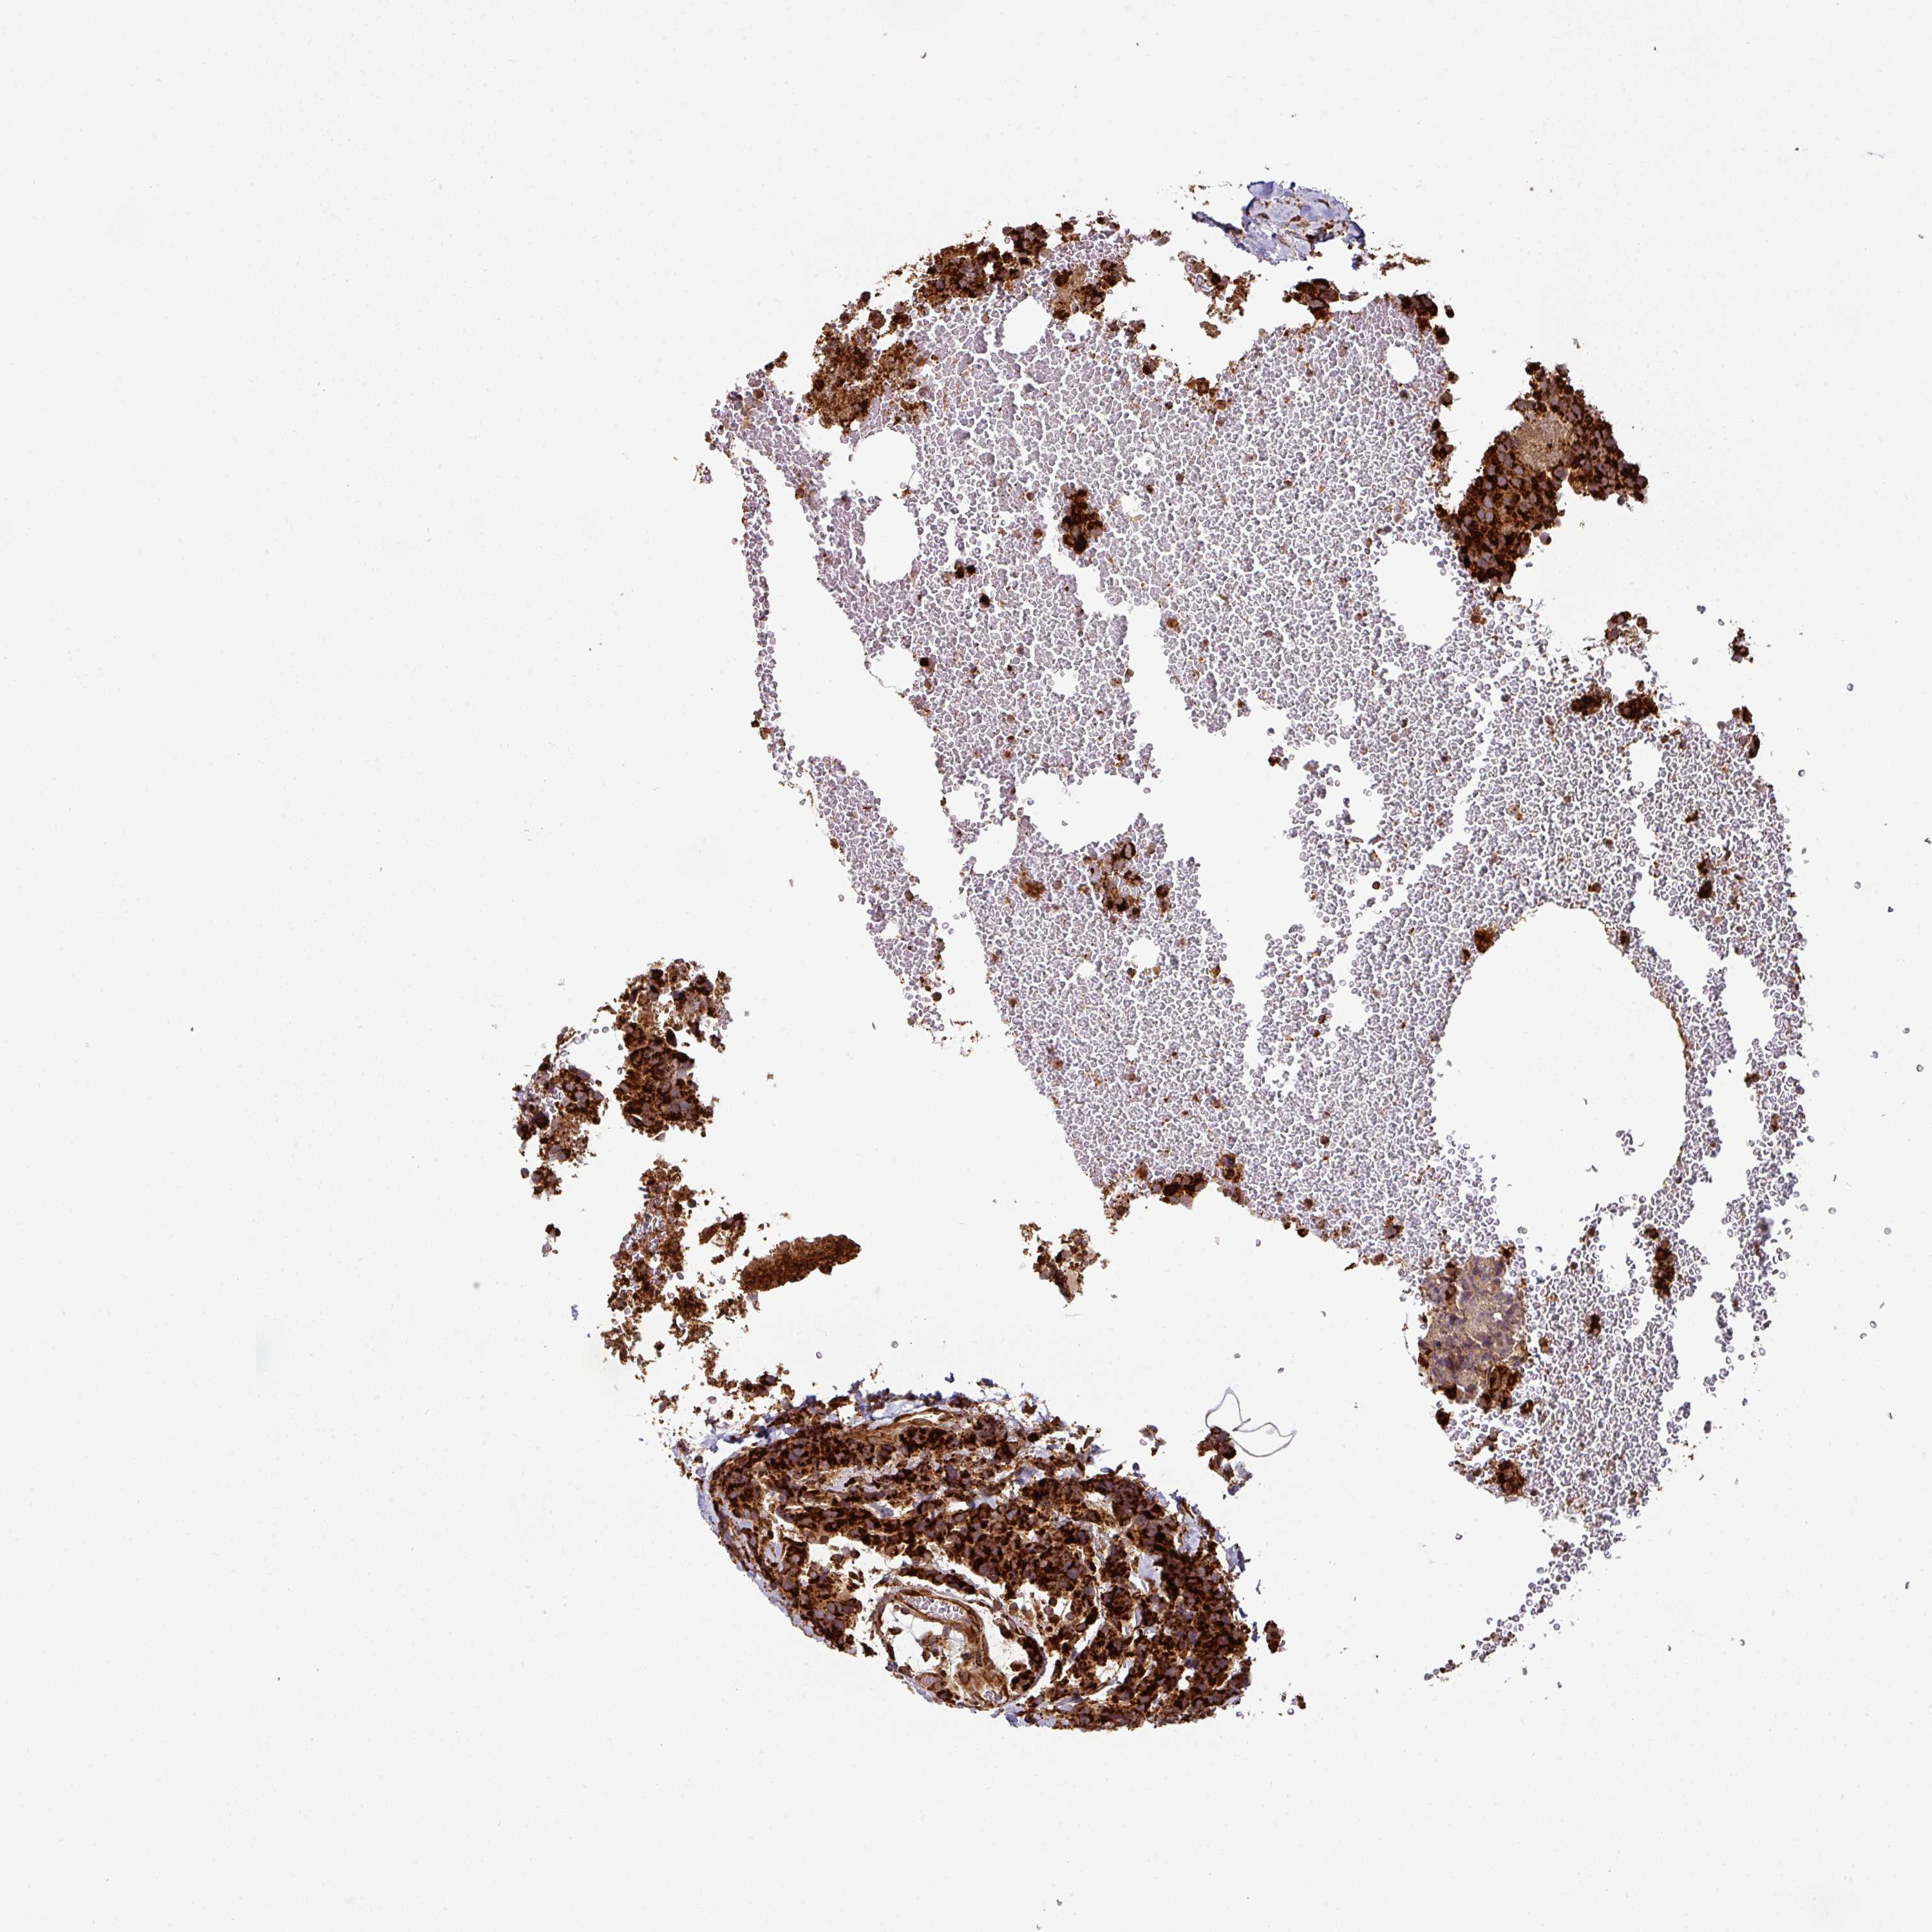

CANCER BREAST CANCER Show tissue menu

BRCA TCGA BRCA VALIDATION PROTEIN EXPRESSION

Breast cancer

Human cancer

TRAP1 is not prognostic in Breast Invasive Carcinoma (TCGA)